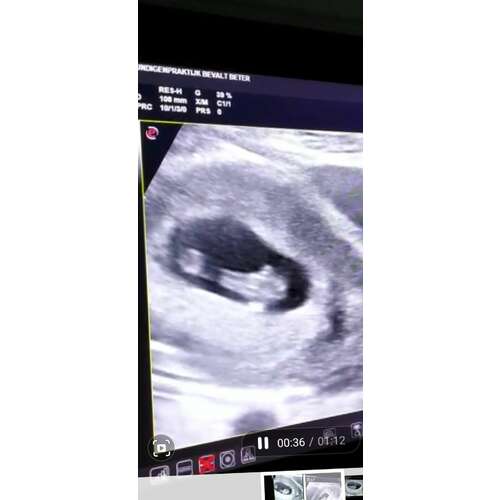

8+3 :) inwendige echo. Ondertussen 9+3 volgende week vrijdag de termijn echo, kan het niet afwachten om weer even te mogen spieken!